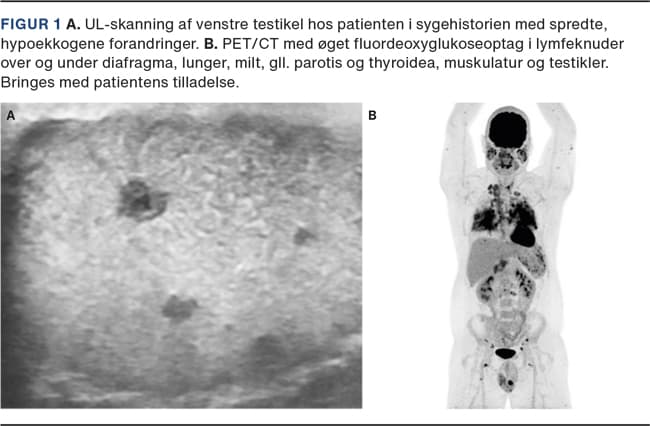

En 29-årig mand, som var tidligere sund og rask, blev i december 2019 henvist til urologisk udredning på mistanke om testikelkræft pga. en nyopdaget knude i venstre testikel. Ved klinisk undersøgelse palperede man en lille, hård tumor i venstre testikels øvre pol. UL-skanning af testiklerne viste spredte, hypoekkogene, velafgrænsede forandringer bilateralt, dog mest udtalt på venstre side, hvor man så en forandring på 9 mm i diameter på stedet for palpationsfundet. Der var normale tumormarkører. På mistanke om patologi i begge testikler, planlagde man bilateral testisbiopsi med frysemikroskopi og eventuelt orkiektomi, forudgået af sæddeponering.

Ved ambulant kontrol i juni 2020 beskrev patienten symptomer i form af hedeture/feberfornemmelse ved indtag af sukkerholdig føde. Man foretog PET/CT, som viste patologisk øget fluordeoxyglukoseoptag i multiple organsystemer, foreneligt med granulomatøs sygdom (Figur 1). Patienten blev henvist til en reumatologisk afdeling på mistanke om sarkoidose. Her blev diagnosen stillet på det samlede kliniske og parakliniske billede, og man iværksatte medicinsk behandling ved første fremmøde. I marts 2021 var behandlingen afsluttet, og patienten var asymptomatisk, men følges fortsat i reumatologisk regi.